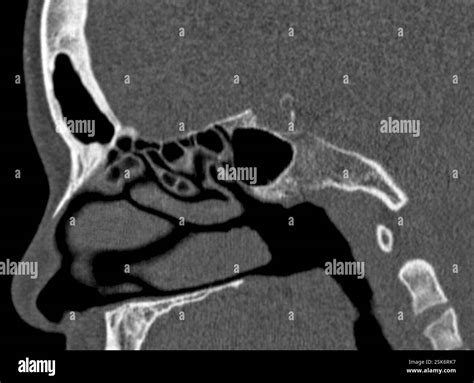

A Normal Sinus CT Scan is a type of computed tomography (CT) scan specifically designed to examine the sinuses, which are the air-filled cavities in the skull. This non-invasive procedure uses X-rays to create cross-sectional images of the sinuses, providing a comprehensive view of their structure and any potential abnormalities. The scan is particularly useful for diagnosing conditions such as sinusitis, nasal polyps, and tumors.

The process of a Normal Sinus CT Scan involves several steps. First, the patient is positioned on a table that slides into the CT scanner. The scanner rotates around the patient, emitting X-rays that are detected by sensors. These sensors then convert the X-ray data into detailed images, which are displayed on a computer screen for the radiologist to analyze.

The results of a Normal Sinus CT Scan are interpreted by a radiologist, who looks for any abnormalities in the sinus structures. The images are analyzed for signs of inflammation, infection, tumors, or other conditions. The radiologist then provides a report to the referring physician, who discusses the findings with the patient.

Common findings in a Normal Sinus CT Scan include:

• Inflammation or swelling of the sinus membranes.

• Presence of fluid or mucus in the sinuses.

• Nasal polyps or other obstructions.

• Bone abnormalities or fractures.

• Tumors or other masses.

If abnormalities are detected, further diagnostic tests or treatments may be recommended based on the specific findings.